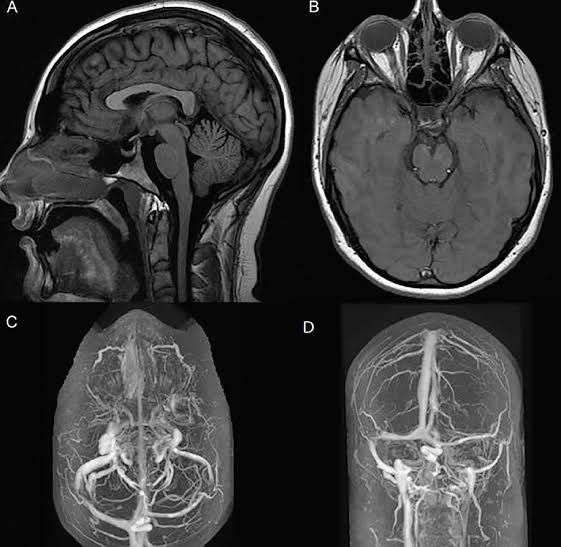

Idiopathic intracranial hypertension (IIH) is a disorder related to high pressure in the brain. It causes signs and symptoms of a brain tumor. It is also sometimes called pseudotumor cerebri or benign intracranial hypertension. The fluid that surrounds the spinal cord and brain is called cerebrospinal fluid or CSF.